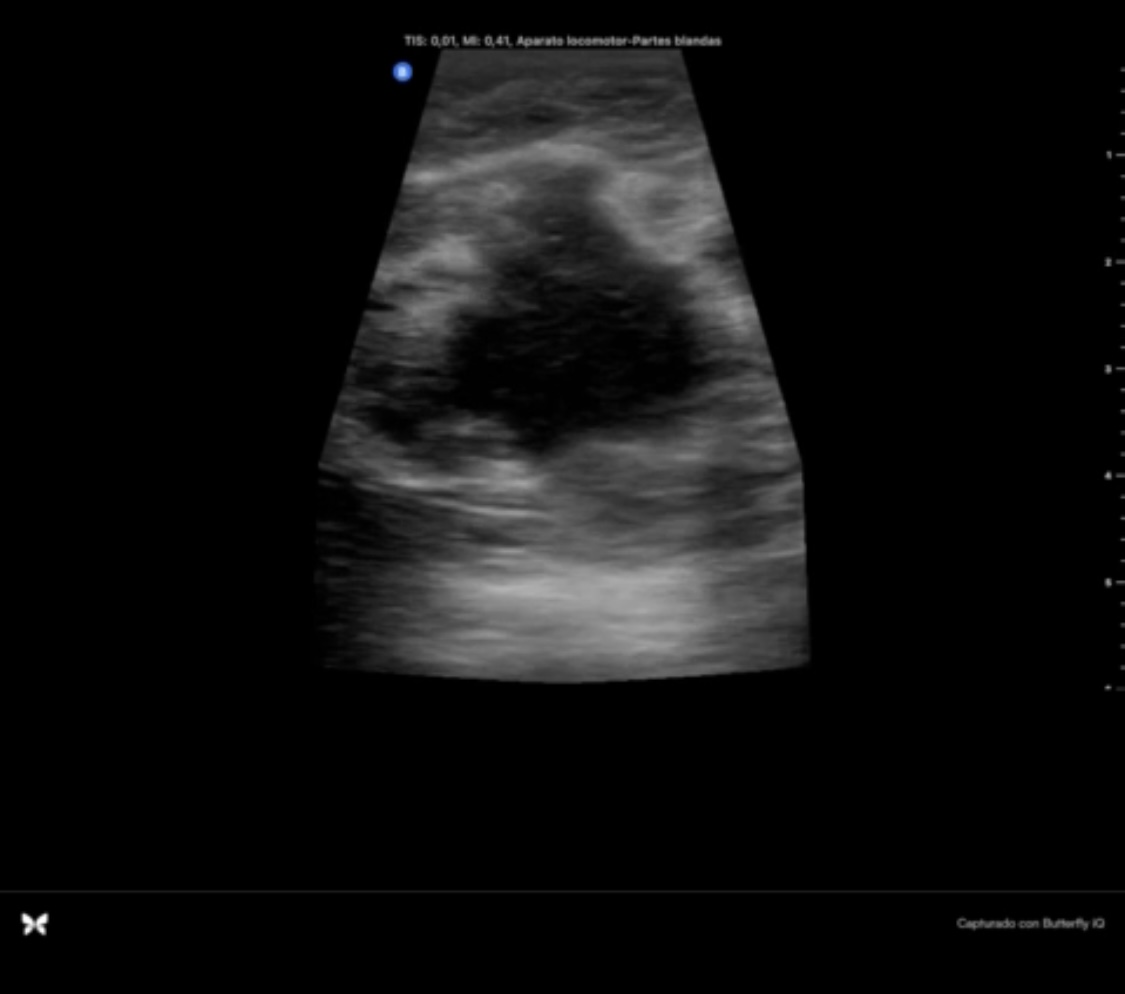

Hallazgos ecográficos

Se objetiva masa hipoecogénica respecto al tejido fibroglandular, heteroecogénica, mal delimitada, más alta que ancha y que no se modifica con la presión de la sonda. En regiones circundantes a la lesión se objetivan lesiones redondeadas, quísticas, que impresionan dilataciones de los conductos galactóforos.